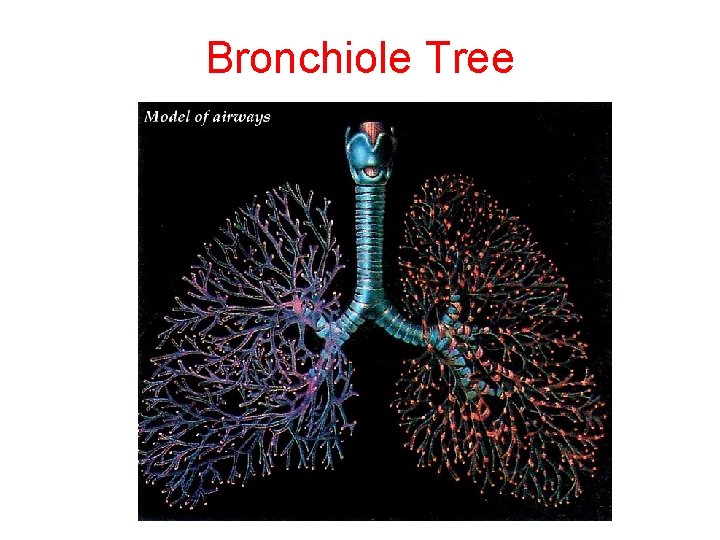

Bronchiole Tree

Bronchiole Tree